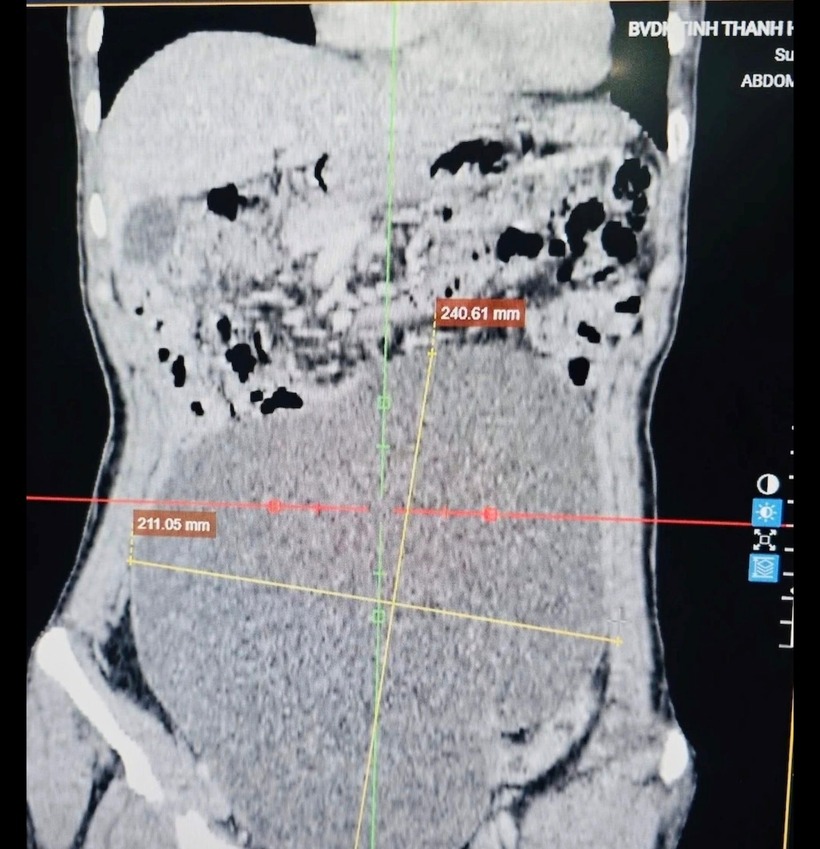

Thông tin trên báo Công lý, Bệnh viện Đa khoa tỉnh Thanh Hóa cho biết, mới phẫu thuật thành công, cắt bỏ khối u buồng trứng nặng gần 3kg cho một nữ bệnh nhân.Theo thông tin, bệnh nhân Trần Thị H. (53 tuổi), hiện sinh sống tại tỉnh An Giang, quê quán Thanh Hóa, nhập viện trong tình trạng đau tức vùng hạ vị lan lên thượng vị, đau âm ỉ kéo dài, thời gian gần đây mức độ đau tăng nhiều.

Tại bệnh viện, kết quả chụp cắt lớp vi tính (CLVT) ổ bụng cho thấy một khối u kích thước rất lớn, chiếm gần toàn bộ ổ bụng, kéo dài từ hạ vị đến thượng vị, xuất phát từ buồng trứng.

Hình ảnh khối u trong cơ thể nữ. Ảnh: Báo Công lý.

Ca phẫu thuật được thực hiện bởi ê-kíp Khoa Ngoại tổng hợp 2 phối hợp với Khoa Gây mê hồi sức, đã bóc tách thành công khối u xuất phát từ buồng trứng trái, kích thước khoảng 25cm, nặng gần 3kg.